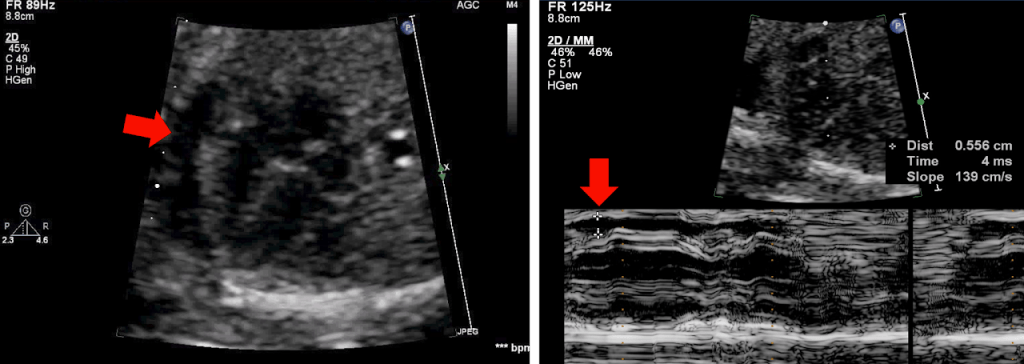

Fetal Echo image showing pericardial effusion(red arrow). 2-D and M-mode images showing the pericardial collection. The maximum diameter is measured irrespective of systole or diastole.